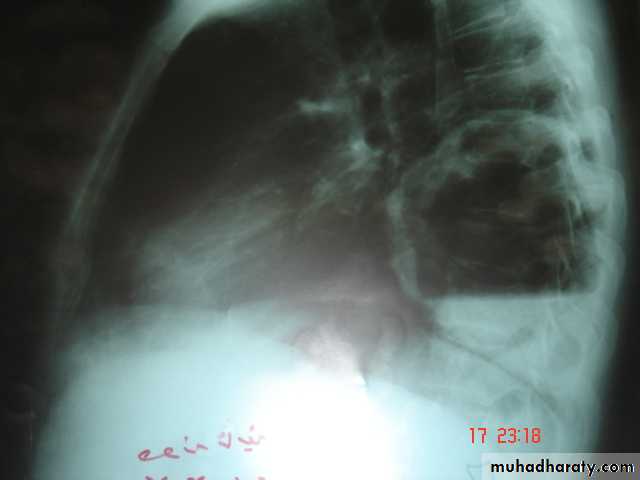

• Lung Abscess It is a localized area of suppuration and cavitations in the lung.It includes TB , mycotic or parasitic cavitations ,bronchiectasis ,ruptured infected hydatid cyst , even pulmonary infarction with abscess formation & cavitating tumors

• Simple lung abscess (pyogenic) can occurs as a result of aspiration of a septic debris from the oropharynx into the lung or following dental or tonsillar operations .

• Esophageal diseases that lead to regurgitation &subsequent aspiration of esophageal content into the lung is another cause.

• Usually the aspiration is into the RMB leading to severe pnemonitis and liquefaction may occurs .As the liquefied necrotic material empties through the bronchus , a necrotic cavity containing pus and air is formed .The organism responsible may be streptococcus , staphylococus &eschrescia coli .

• Clinically cough & foul smelling sputum fever , pleuritic chest pain night sweat & weight loss in severe cases dyspnea & cyanosis

• Chest X-Ray

• Can shows the characteristic air fluid level ,may associated with pleural thickening , pneumothorax

• CT chest is helpful in demonstrating the abscess .